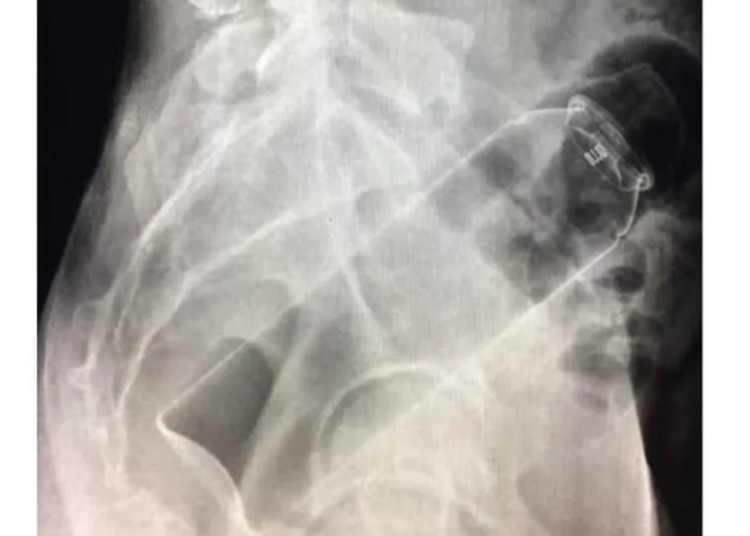

De acordo com informações apuradas pela equipe do Jornal Eletrônico Portal de Rondônia, o homem teria introduzido o frasco de desodorante no ânus, no entanto, o objeto acabou ficando preso, e ele não conseguiu removê-lo.

Em pânico, o empresário entrou no carro, modelo Volkswagen Virtus, e dirigiu até um hospital particular da cidade em busca de socorro médico. No local, os profissionais de saúde realizaram o procedimento para a retirada do desodorante, que foi bem-sucedido.